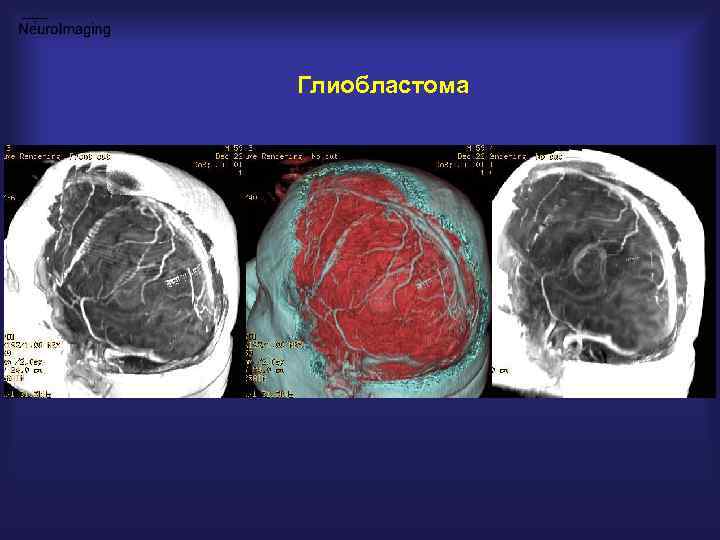

Глиобластома

МРТ в планировании операционного доступа Глиобластома